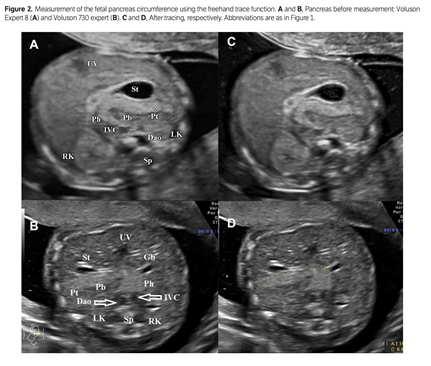

Kivilevitch et al., The Normal Fetal Pancreas, J Ultrasound Med 2017; 36:1997–2005

Beispiel Pankreasumfang

Tabelle Pankreasumfang